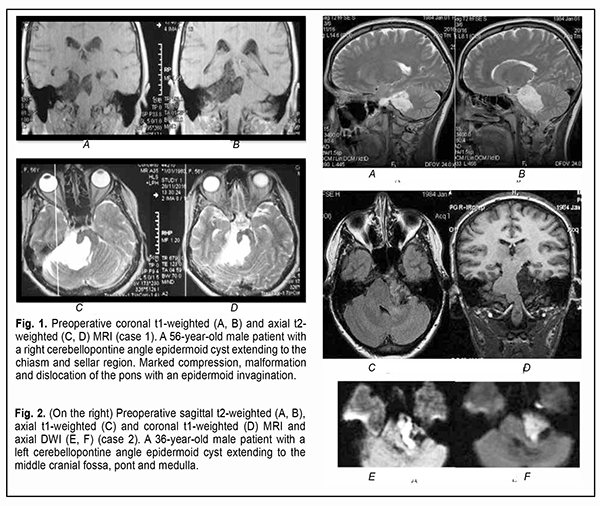

Introduction Epidermoid cysts manifest themselves clinically predominantly between the ages of 20 and 50 years, most commonly occur in the skull base, and usually arise in the subarachnoid cisterns, cerebellopontine angle and parasellar region. They grow slowly and can attain a large size before the onset of neurological symptoms. As the neoplasm grows, it gradually presses on, displaces and envelops the cranial nerves (CN) and adjacent vessels, and frequently invaginates the brainstem, causing ophthalmological abnormalities and lesions of relevant CN (Fig.1, 2, 3) [1, 2, 3].

Of the 21 patients, 7 (33.33%) had a gross total removal and 2 (9.53%) had a near total removal of the cyst, with residual capsule fragments not exceeding 2-3 mm (Figs. 4, 5, 6, and 7). In addition, 12 (57.14%) had a subtotal removal of the cyst, with either intraoperative evidence of residual capsule fragments measuring from 2 mm to 10 mm, or postoperative MRI evidence of residual capsule fragments not exceeding 11 mm in the largest dimension. The capsule adhesion to surrounding neurocascular structure at the location where the dissection was difficult was seen in 18 patients (85.7%). In some cases, this can lead to the impossibility of safe total capsule dissection from the brainstem and cranial nerves. Postoperative follow-up ranged from 1 to 12 years, with mean and median values of 38.5 ± 4.8 months and 24 months, respectively (Fig. 8).